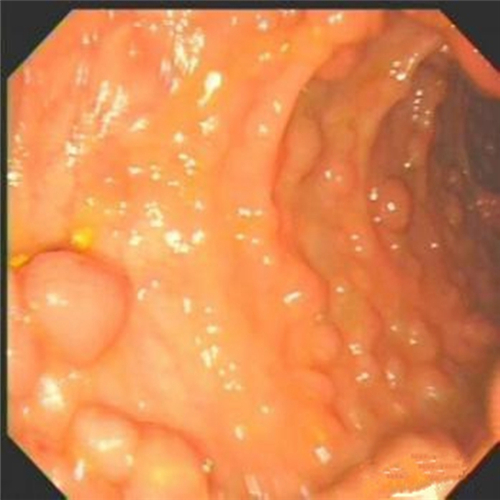

直腸息肉良性

直腸息肉糜爛的